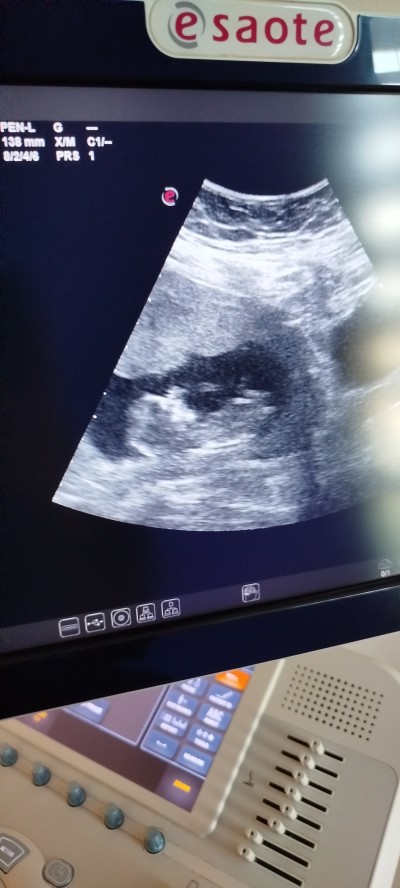

Cinsiyet tahmini yapabilir misiniz sizce nedir

Gebelik haftası 13+2

Erkekkkkk benceee